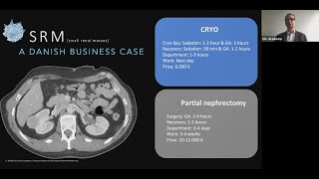

Cryoablation of renal tumors: Treating more patients per day – Is conscious sedation the solution?

Sep 29, 2020

External Link( 5.0 MB )

Prof. Ole Graumann provides tips and tricks for treating the right RCC patients with conscious sedation including needle placement and post treatment recovery.

Renal Cryoablation – Conscious sedation and optimization of patient workflow

Sep 12, 2020

External Link( 16.0 KB )

Prof. Ole Graumann introduces different conscious sedation methods and explains how it can optimize patient workflow in a cost effective way.